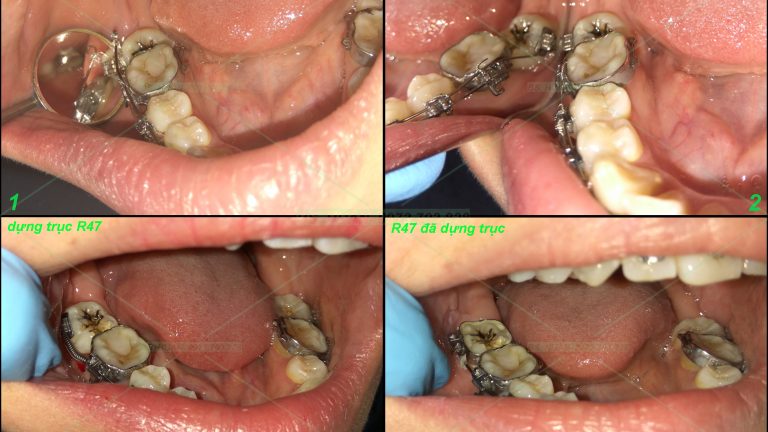

tiếp nối 1 số ca lẻ P1 Bạn D.H.L nữ 36 tuổi đến niềng hàm dưới để đóng kín khe thưa, bạn này thiếu 1 răng cửa dưới và kết quả sau 3 tháng hàm dưới đã đều và kín khe thưa. Bạn N.N.P.L nữ 12 tuổi đến niềng vì muốn làm […]